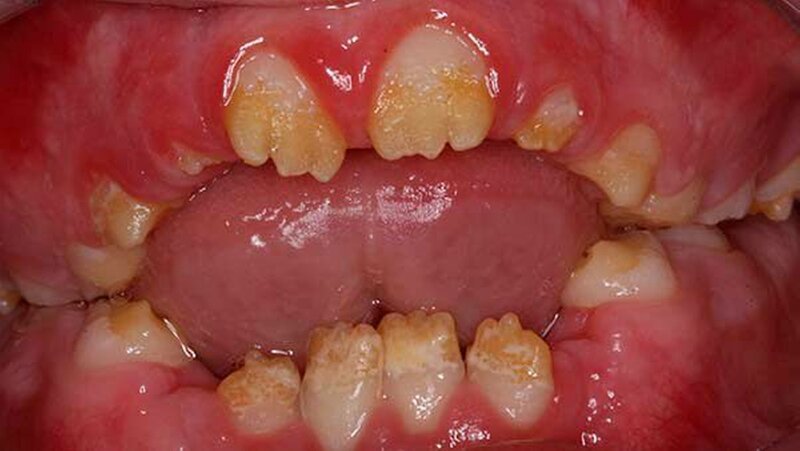

Der zehn Jahre alte Junge stellte sich an der Klinik wegen Schmerzen im ganzen Mund vor. Zusätzlich klagte der Patient über die eingeschränkte Möglichkeit Speisen ab zu beißen (Abbildung 1a und Abbildungen 3a und 3b). Die Familienanamnese ergab eine nahe verwandtschaftliche Verheiratung in der Familie. Das dentale Erscheinungsbild konnte von den Eltern des Patienten in der Verwandtschaft jedoch ausgeschlossen werden.

Der klinische Befund zeigte an beiden Dentitionen eine rauhe, zum Teil verminderte, bis fehlende Schmelzdicke und eine teilweise bräunliche Zahnverfärbung. Letztere wurden auch durch exogene Pigmenteinlagerung verursacht (Abbildung 1b und Abbildung 2).